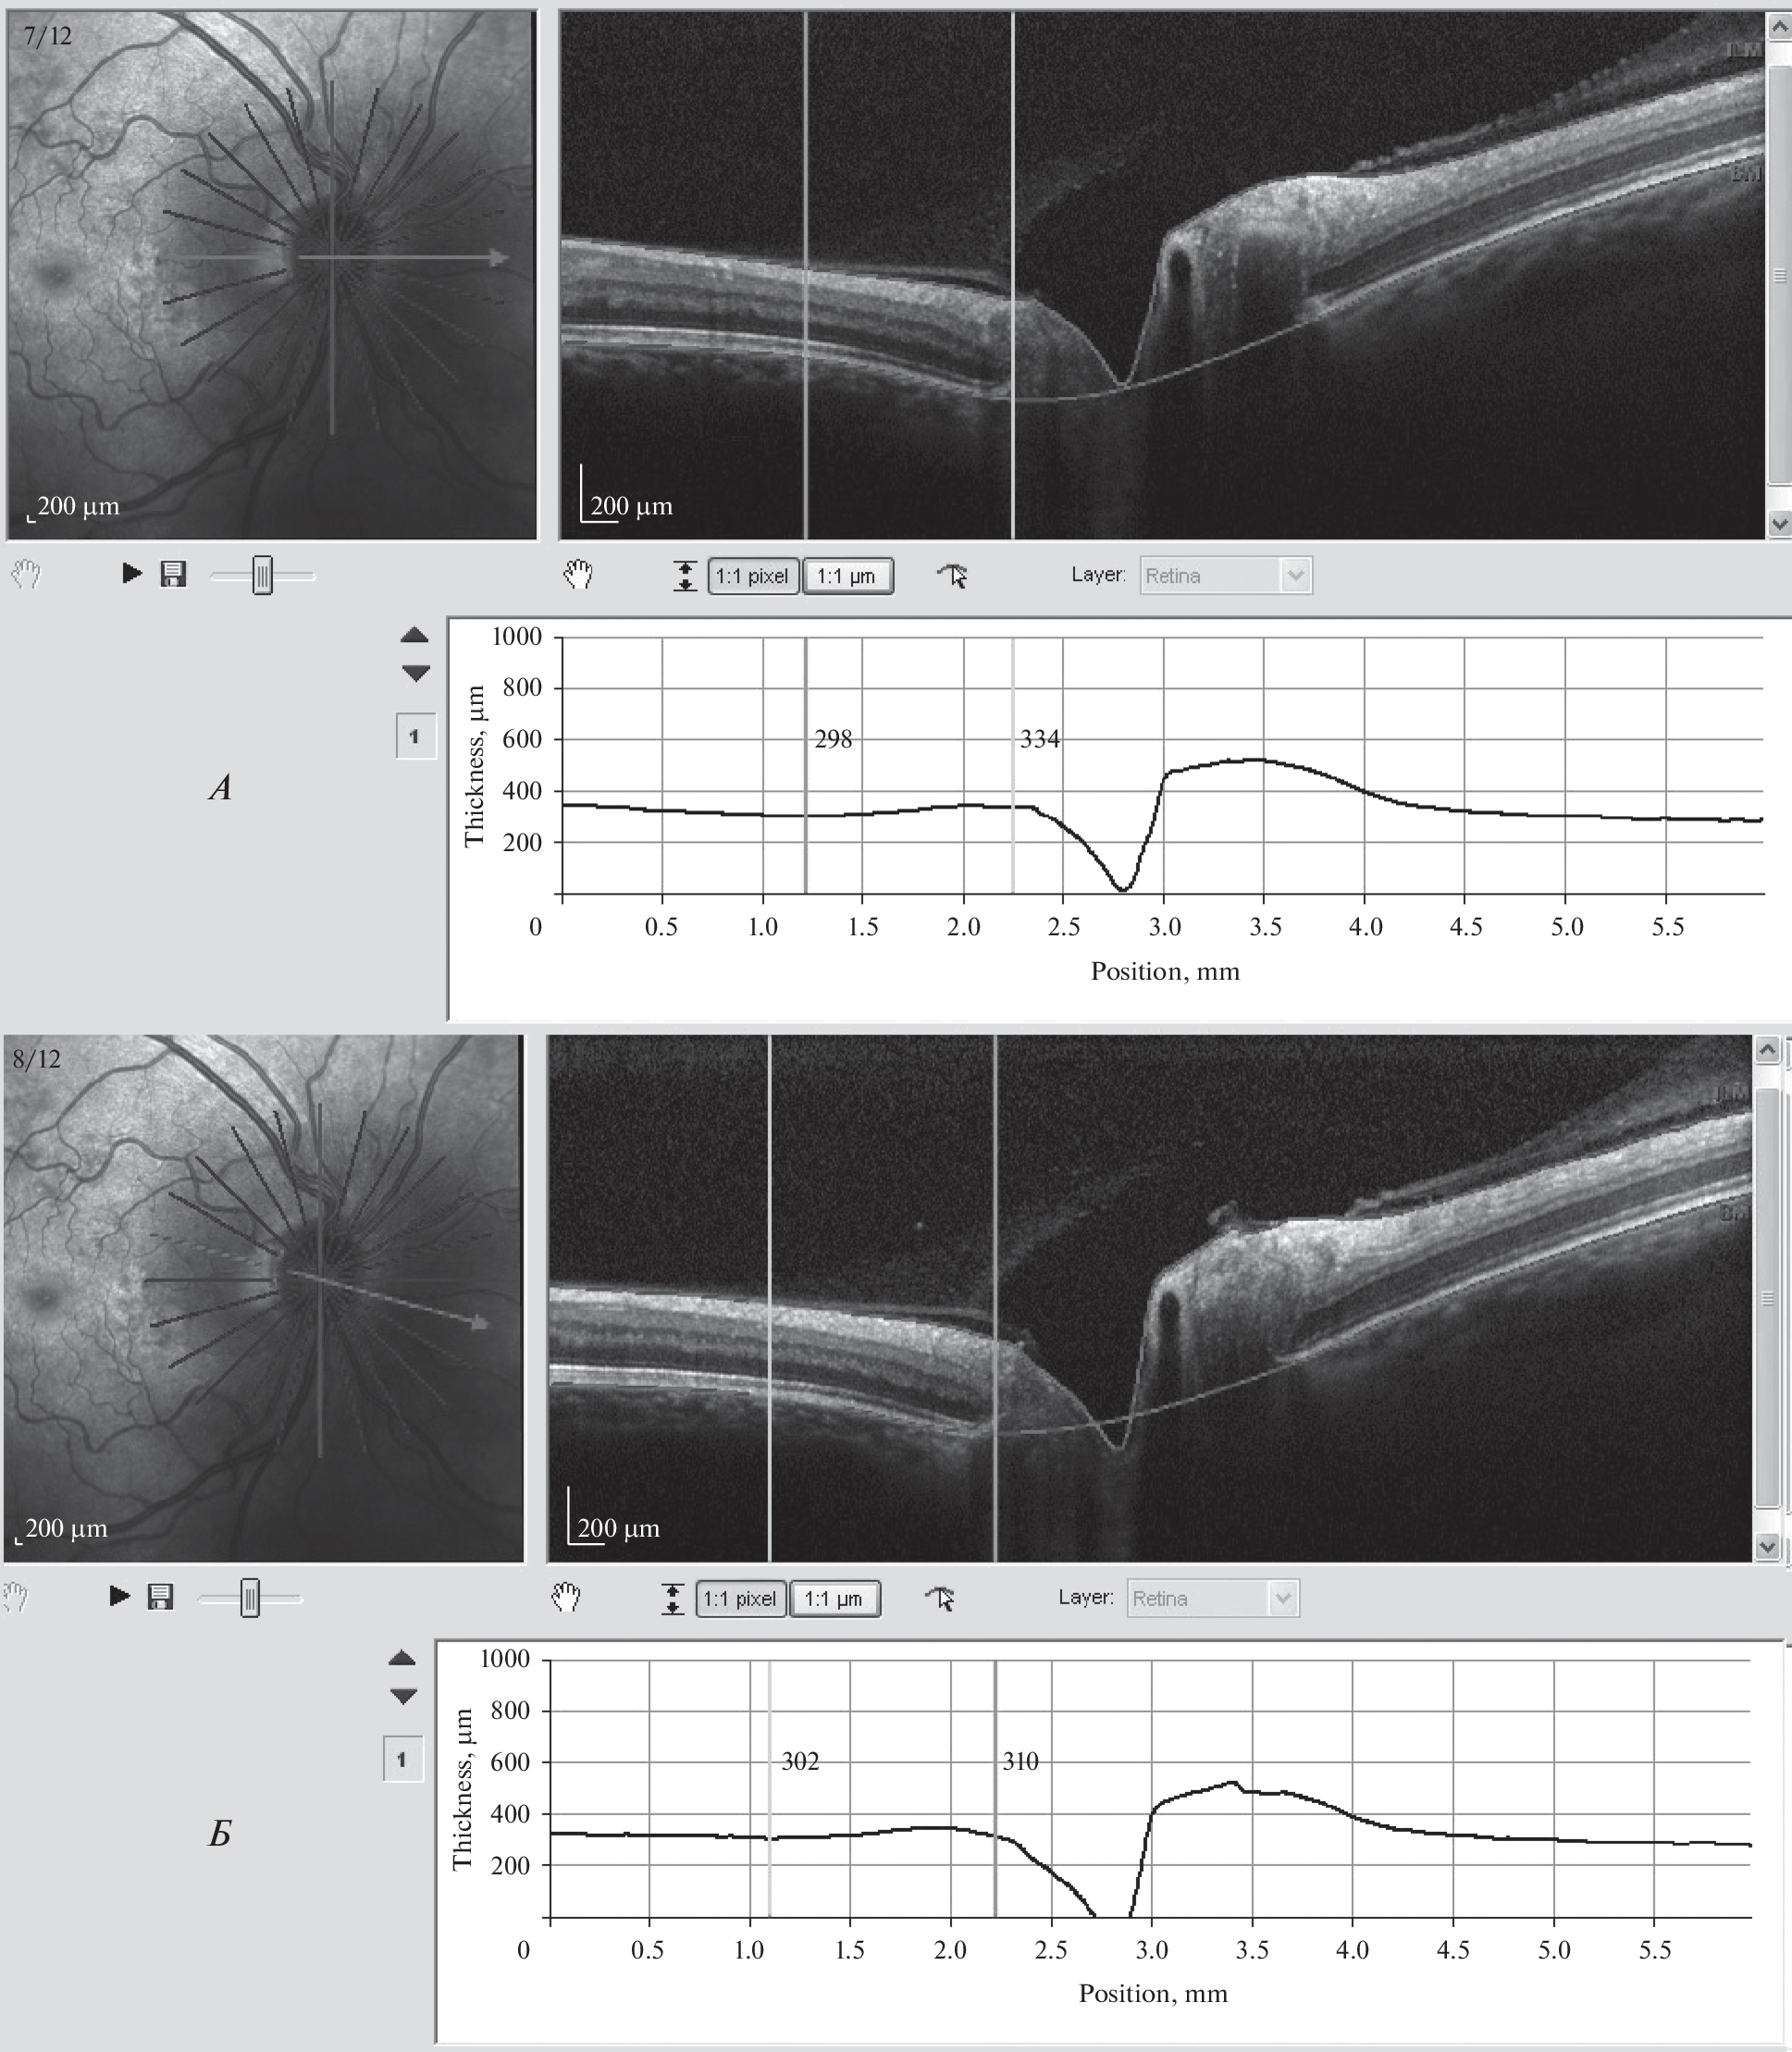

В данной статье анализируется состояние 24 глаз 12 российских космонавтов, совершивших длительные космические полеты (КП) на международной космической станции (МКС) в период с 2016 по 2021 гг. В работе на изображениях, полученных с помощью оптического когерентного томографа Spectralis OCT + HRA, путем использования прилагаемых в программе вычислительных функций определена толщина головки зрительного нерва и сетчатки по часовым меридианам, что позволило точно диагностировать и классифицировать отек диска зрительного нерва (ДЗН) по стадиям шкалы Frisen. Путем измерения процентного соотношения максимальной толщины ДЗН в его границах к минимальной величине толщины сетчатки вне границ ДЗН определили цифровое значение проминенции в каждом височном часовом меридиане, ограниченным височным сектором в 95°. Наличие проминенции в крайних височных часовых меридианах или вовсе ее отсутствие расценивали как физиологически здоровое состояние ДЗН, соответствующее 0 стадии. Эта стадия установлена на 13 глазах (54.2%). I стадия (7 глаз (29.2%)) диагностирована на основании отсутствия проминенции в горизонтальном височном меридиане. Определяющим признаком II стадии является увеличение проминенции в височном горизонтальном меридиане больше, чем на 10%. Субклиническая II стадия (проминенция увеличена, но меньше, чем на 10%) установлена на двух глазах двух космонавтов (8.3%). Клинически выраженная папилледема II–III стадии диагностирована на двух глазах (8.3%) у одного космонавта, где максимальная величина проминенции составляла на правом глазу 70.1%, а на левом – 40.1% в горизонтальном часовом меридиане. Исследование показывает, что увеличение проминенции до 70% в височном горизонтальном часовом меридиане при III стадии отека приводит к нейродегенерации волокон зрительного нерва в КП. При II–III стадии отека отмечено увеличение минимальной толщины нейроретинального пояска по сравнению со всеми остальными наблюдениями. При 0–II субклинической стадии по этому показателю невозможно было дифференцировать состояние ДЗН.